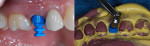

Implant impressions are taken as either a closed-tray or an open-tray technique. For a closed-tray technique, a tray for a full-arch dentate impression is used even if the arch has no natural teeth. This will allow space for the impression heads and sufficient impression material to capture the impression head within the material and tray. If an open-tray technique is chosen, two options are available. A full-arch dentate tray can be used and holes in the occlusal surface can be cut in order to allow the long impression pin to protrude through the tray once inserted, filled with impression material. It is advised that prior to inserting the tray filled with impression material, the tray be tried in after the occlusal holes have been created in order to verify that the pins protrude through the tray. The holes can be moved or enlarged as needed until they are visible through the tray, and then the impression can be captured. It is important that upon insertion of the filled tray, impression material be wiped from the top of the pins and visualization of all pins is noted while the impression is setting.

Another alternative with open-tray impressions is the Miratray® impression tray (Hager Worldwide, www.hagerworldwide.com). These are unique trays designed specifically for open-tray impressions. The occlusal tray surface is covered with a clear film, eliminating the need to cut occlusal holes. The filled tray is inserted until the pins perforate the clear film, making it easier than when using a tray with holes placed occlusally (Figure 6).

Open-tray impressions require that the impression abutment be accurately retained within the impression, so utilization of a stiffer material is critical. Use of a universal body or putty works best with this technique. One aspect to remember, prior to removal of the set impression, is that all the long pins must be removed; otherwise, impression removal cannot be accomplished without damage to the impression (Figure 9).

Whether using an open tray or a closed tray, in order to eliminate voids at the gingival aspect of the impression around the impression heads, a small amount of impression material of a less viscous nature is injected before seating the tray filled with impression material. A medium-body material can be used for both the open- and closed-tray techniques. Using an intraoral tip on the impression gun, a small amount of material is placed circumferentially around each impression head. With the open-tray method, it is important that only the gingival aspect of the impression abutment have the medium-body material placed around it so that the stiffer material is in intimate contact with the impression abutment. The tendency is for the practitioner to completely cover the impression coping, which may allow micromovement of the impression abutments in relation to each other, affecting the accuracy sought.